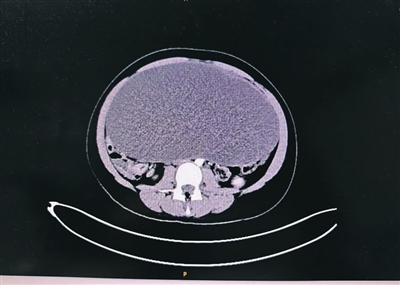

小玲(化名)今年13岁,本该是活力四射的年纪。近期,她常感到腹部膨隆,胀痛不适,甚至影响到了日常活动和饮食。在家人的陪伴下,小玲来到通大附院妇产科主任医师叶青门诊就诊。经过详细检查,结果令人震惊:小玲的盆腔内竟藏着一个直径约25厘米的巨大卵巢囊肿!如此巨大的囊肿在如此年轻的患者身上实属罕见,它已严重压迫腹腔脏器,如不及时处理,不仅痛苦加剧,更存在扭转、破裂甚至影响未来生育功能的巨大风险。